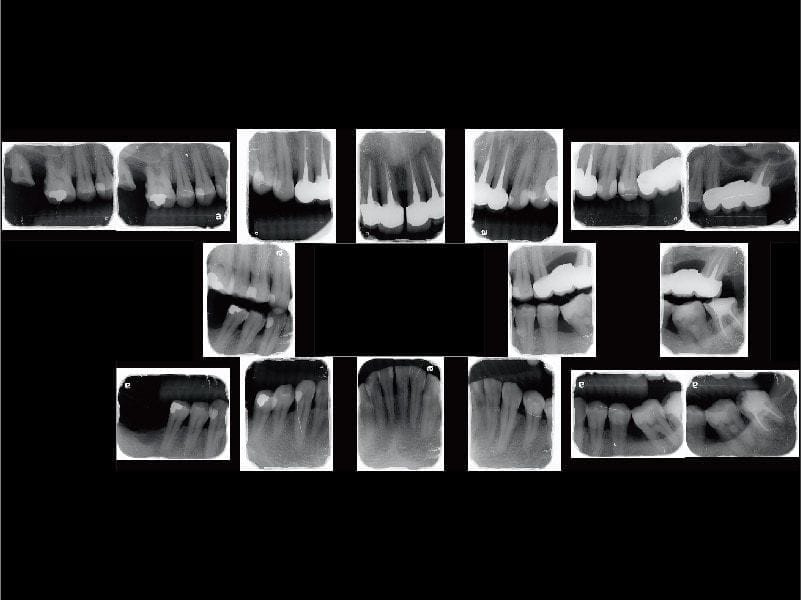

在全口牙周病治療方面,我們做了完整的牙周特別檢查,以達到更精確診斷。一顆牙齒我們通常會測量六個位置的牙周囊袋,才能夠清楚顯示患齒的牙周狀態。

配合測量的深度和X光片上顯示齒槽骨流失的狀況,可以估計整體或單獨牙齒的『預後』,即可能可以維持多久。因為部分區域的齒槽骨已經流失50%以上,診斷為全口中等至嚴重牙周病。

圖示:Mr.Lin診斷為全口中等至嚴重牙周病,需分區治療穩定牙周狀況

進行MAPCare整體複合式牙周第一階段治療,在兩個月左右的時間分區治療,以控制牙周狀況初期穩定,同時也改善患者的口腔衛生習慣。牙周治療就像是先完成了環境大掃除,將來就進入到重建階段。